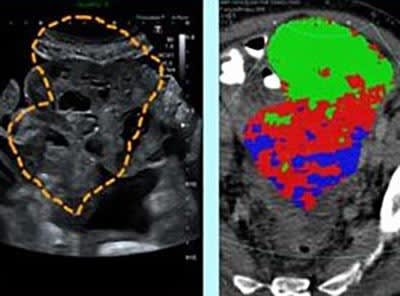

The researchers then used a process called radiomics – using high-powered computing methods to analyze and extract additional information from the data-rich images created by the CT scanner – to identify and map distinct areas and features of the tumor. The tumor map was then superimposed on the ultrasound image of the tumor, and the combined image was used to guide the biopsy procedure.

By taking targeted biopsies using this method, the research team reported that the diversity of cancer cells within the tumor was successfully captured. “This study provides an important milestone towards precision tissue sampling. We are truly pushing the boundaries in translating cutting-edge research to routine clinical care,” said Sala.